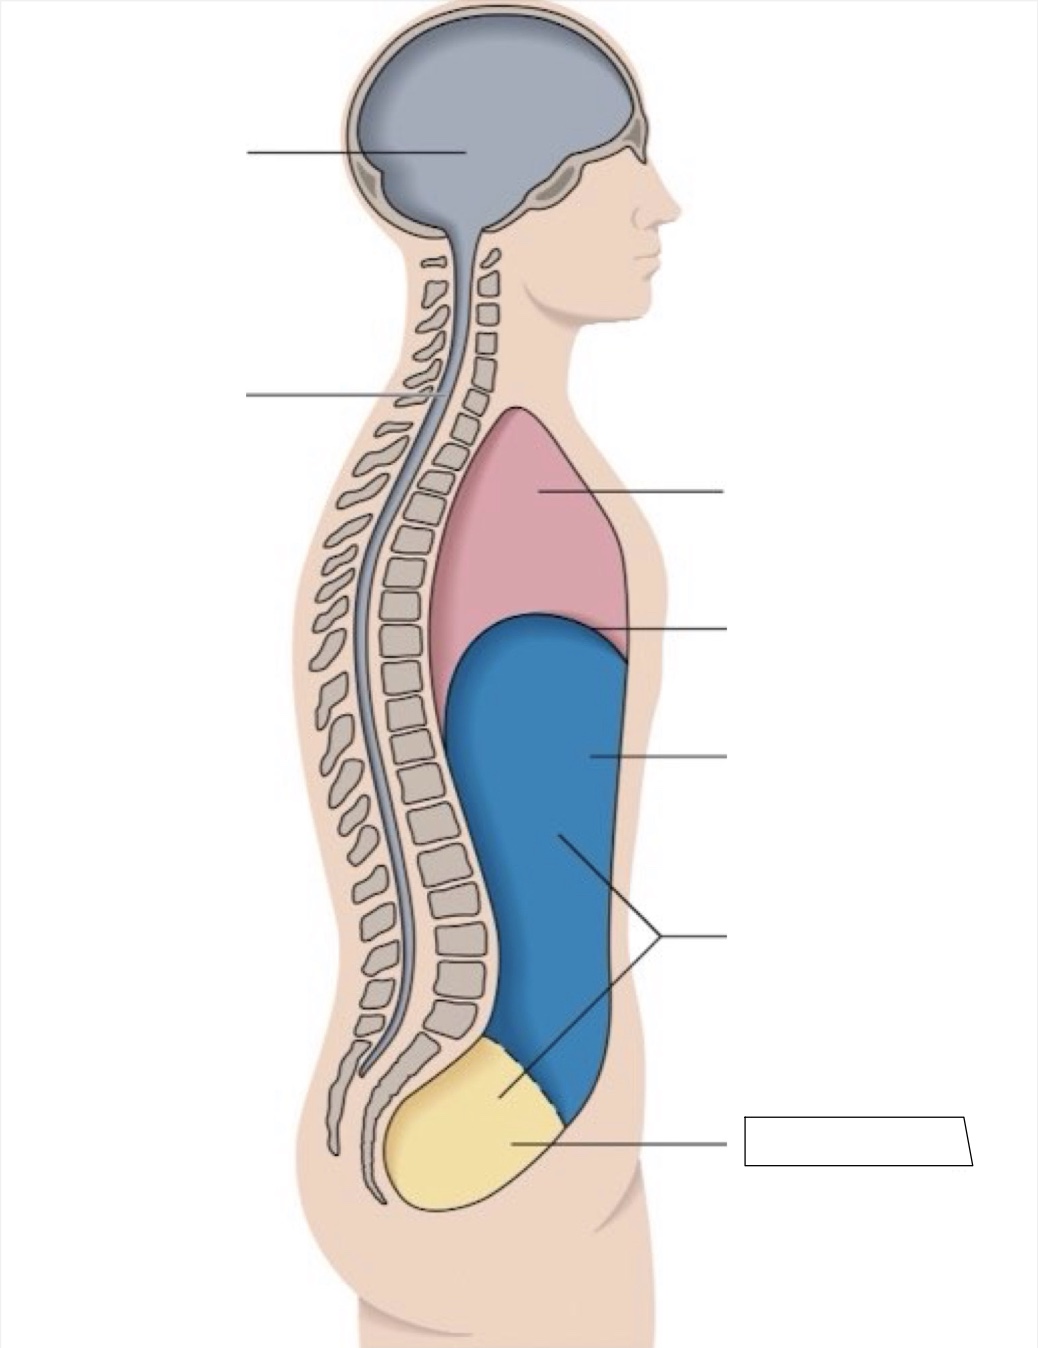

thoracic cavity

diaphragm

abdominal cavity

abdomino-pelvic cavity

pelvic cavity

spinal cavity

cranial cavity